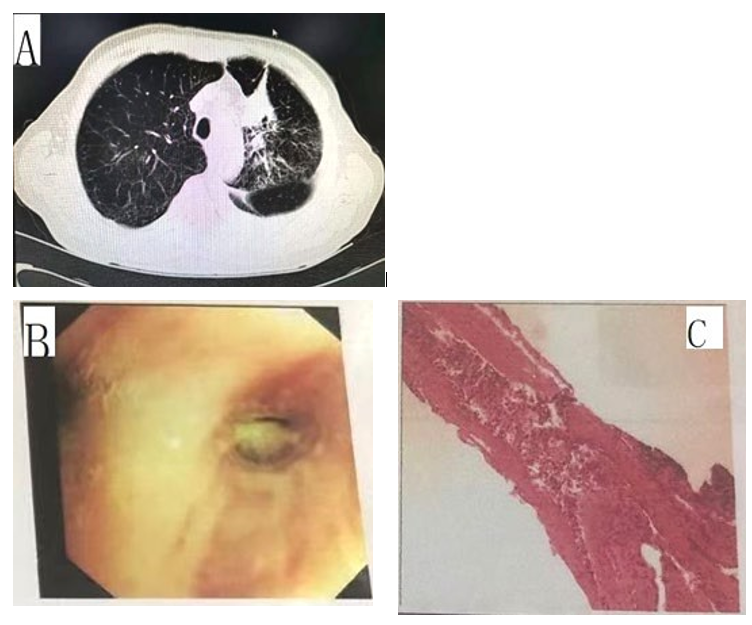

The patient, an 82-year-old male, had underlying “chronic ob- structive pulmonary disease, chronic pulmonary heart disease, and coronary atherosclerotic heart disease”. On September 5, 2018, the patient underwent a chest CT due to aggravated cough and more acute shortness of breath than usual, which revealed a mass-like soft tissue density shadow in the left upper lobe (neoplasms cannot be excluded), left pleural thickening, and left pleural effusion (Fig. A). Tumor marker test on admission revealed carcinoembryonic antigen 70.94 ng/mL, neuron-specific enolase 21.72 ng/mL, cy- tokeratin 19 fragment 14.5 ng/mL, carbohydrate antigen CA-125 104.4 U/mL, and squamous cell carcinoma antigen 2.65 ng/mL. Bronchoscopy showed swelling and stenosis of the mucosa in the anterior segment of the left upper lobe, widening of the cristae, and a few nodular proliferations (Fig. B). Bronchoscopic biopsy pathology of the anterior segment of the left upper lobe showed moderately differentiated squamous cell carcinoma, immunohis- tochemistry: CK5/6 (+), P40 (+), p63 (+), CK7 (−), TTF-1 (−), NapsinA (−), and Ki-67 index 10% (Fig. C). The family refused further treatment because of the patient’s advanced age, underly- ing diseases, and poor cardiopulmonary function. On September 28, 2018, the patient’s shortness of breath worsened again, and a chest CT revealed that the amount of left pleural effusion was significantly increased compared to the previous test.

Figure A: chest CT revealed a mass-like soft tissue density shadow in the left upper lobe (neoplasms cannot be excluded), left pleuralthickening, and left pleural effusion.

Figure B: Bronchoscopy showed swelling and stenosis of the mucosa in the anterior segment of the left upper lobe, widening of the cristae, and a few nodular proliferations.

Figure C: Bronchoscopic biopsy pathology of the anterior segment of the left upper lobe showed moderately differentiated squamous cell carcinoma, immunohistochemistry: CK5/6 (+), P40 (+), p63 (+), CK7 (−), TTF-1 (−), NapsinA (−), and Ki-67 index 10%.